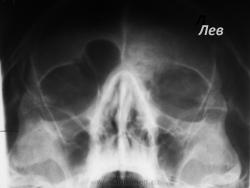

Складывается впечатление, что правая лобная пазуха представлена избыточно развитой ячейкой решетчатой кости - псевдолобная пазуха, левая пазуха отсутствует, возможно, изначально. Верхнечелюстные пазухи не настораживают. Сделать обзорную краниографию в прямой и левой боковой проекции, а далее - томограммы. Думаю, так.

О синуите речь не идет, а вот что касается левой лобной пазухи - прицельный снимок в левой боковой проекции, цель - дифференциация между аномалией (аплазия) и остеомой смешаного характера; если сомнения останутся - КТ.

на обычный синусит неочень похоже, контуры стенок пазухи не дифференцируются вообще, еще и верхняя часть глазницы пострадала. Пока мысли об онко...мукоцеле... Дообследование обязательно, ЛОР сам определит алгоритм действия.

Мукоцелле в лобной слева?

Остеохондрома верхнемедиальной стенки левой орбиты.

Спасибо всем за отзывы! Снимок один-единственный, пациент не явился на дообследование. Конечно, рекомендовала боковой. Потом планировала КТ, если останутся вопросы. На момент публикации экспертизы, у меня ничего из даных о нем не было. Я дала описательную картину, мне было неясно, что с лобной. Но воз и ныне там, зашла к ВОП, амбулаторная карточка ничего не привлесла: ОРЗ, гастрит. Синуситов не было. Пациент больничный не брал, записано, что не работает. Кровь-мочу сдал, там все нормально. И на прием он больше не пришел.

Так что на сегодняшний день загадка не разгадана.